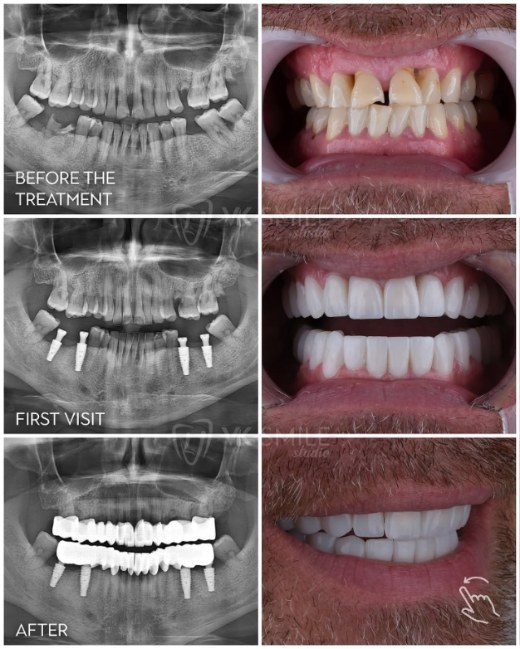

Erster Besuch (5-7 Tage in der Türkei)

Tag 1: Ankunft, Hoteltransfer und erste Konsultation. Der Zahnarzt führt eine umfassende Untersuchung durch, erstellt 3D-Scans und plant die Implantatpositionierung.

Tag 2: Chirurgischer Eingriff. Die Implantate werden unter lokaler Betäubung oder Sedierung eingesetzt. Dies dauert etwa 2-3 Stunden pro Kiefer. Sie erhalten temporäre Zähne am selben Tag, sodass Sie nie zahnlos sind.

Tag 3-4: Erholungszeit. Leichte Beschwerden sind normal und werden mit Medikamenten behandelt.

Tag 5-7: Kontrolluntersuchung und Anpassungen der temporären Zähne. Sie erhalten detaillierte Pflegeanweisungen und können nach Hause reisen.

Einheilphase (3-6 Monate)

Während dieser Zeit heilen die Implantate ein und verwachsen mit dem Kieferknochen (Osseointegration). Sie tragen während dieser Phase Ihre temporären Zähne, die vollständig funktionsfähig sind.

Zweiter Besuch (3-5 Tage in der Türkei)

Nach erfolgreicher Einheilung kehren Sie für die finalen Restaurationen zurück. Der Zahnarzt nimmt präzise Abdrücke, passt Farbe und Form an und setzt die permanenten Porzellan- oder Zirkonoxid-Zähne ein. Nach finalen Anpassungen und Kontrollen ist Ihre Behandlung abgeschlossen.